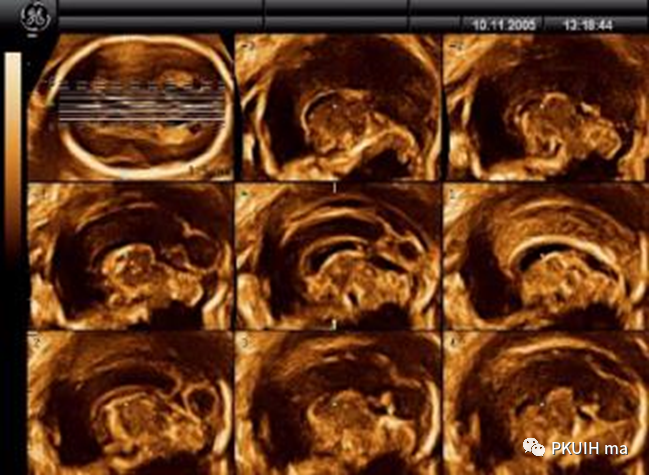

TUI模式一个图像包括了整个颅脑结构,简单直观